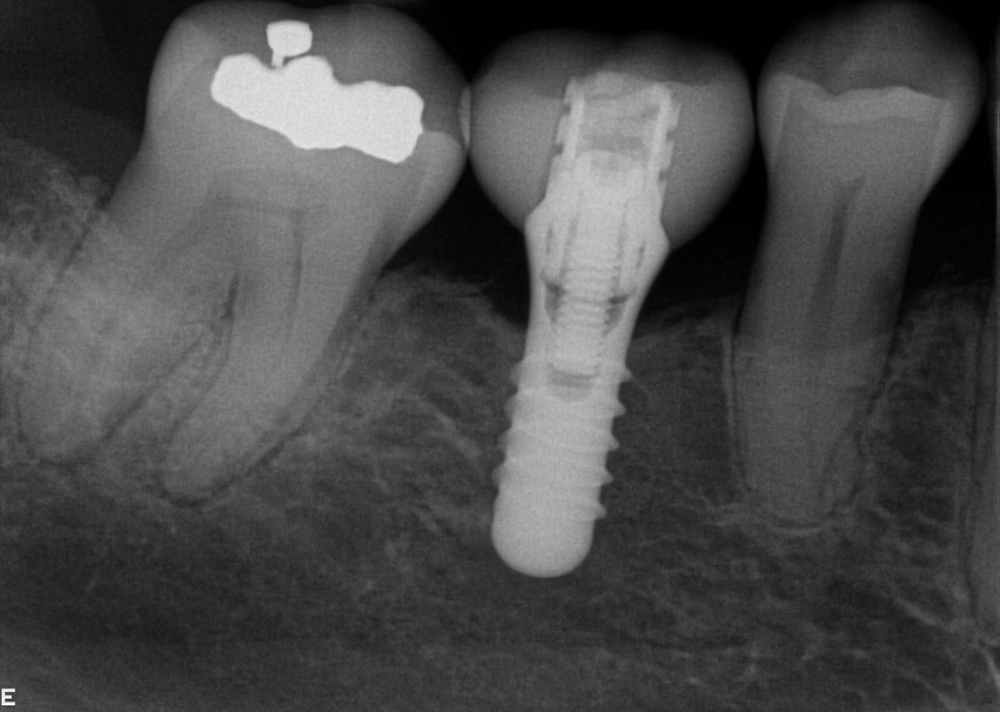

Tooth no. 19 was isolated with a dental dam under local anesthesia. All existing restorative material and decay was excavated leaving a very evident crack into the pulp, down to the pulpal floor. The mesial canals were completely calcified, the decay extended beyond the bone level. This tooth was diagnosed as hopeless and scheduled for removal. A provisional was placed at this appointment.

Tooth no. 30 was deemed hopeless at initial evaluation and extracted.